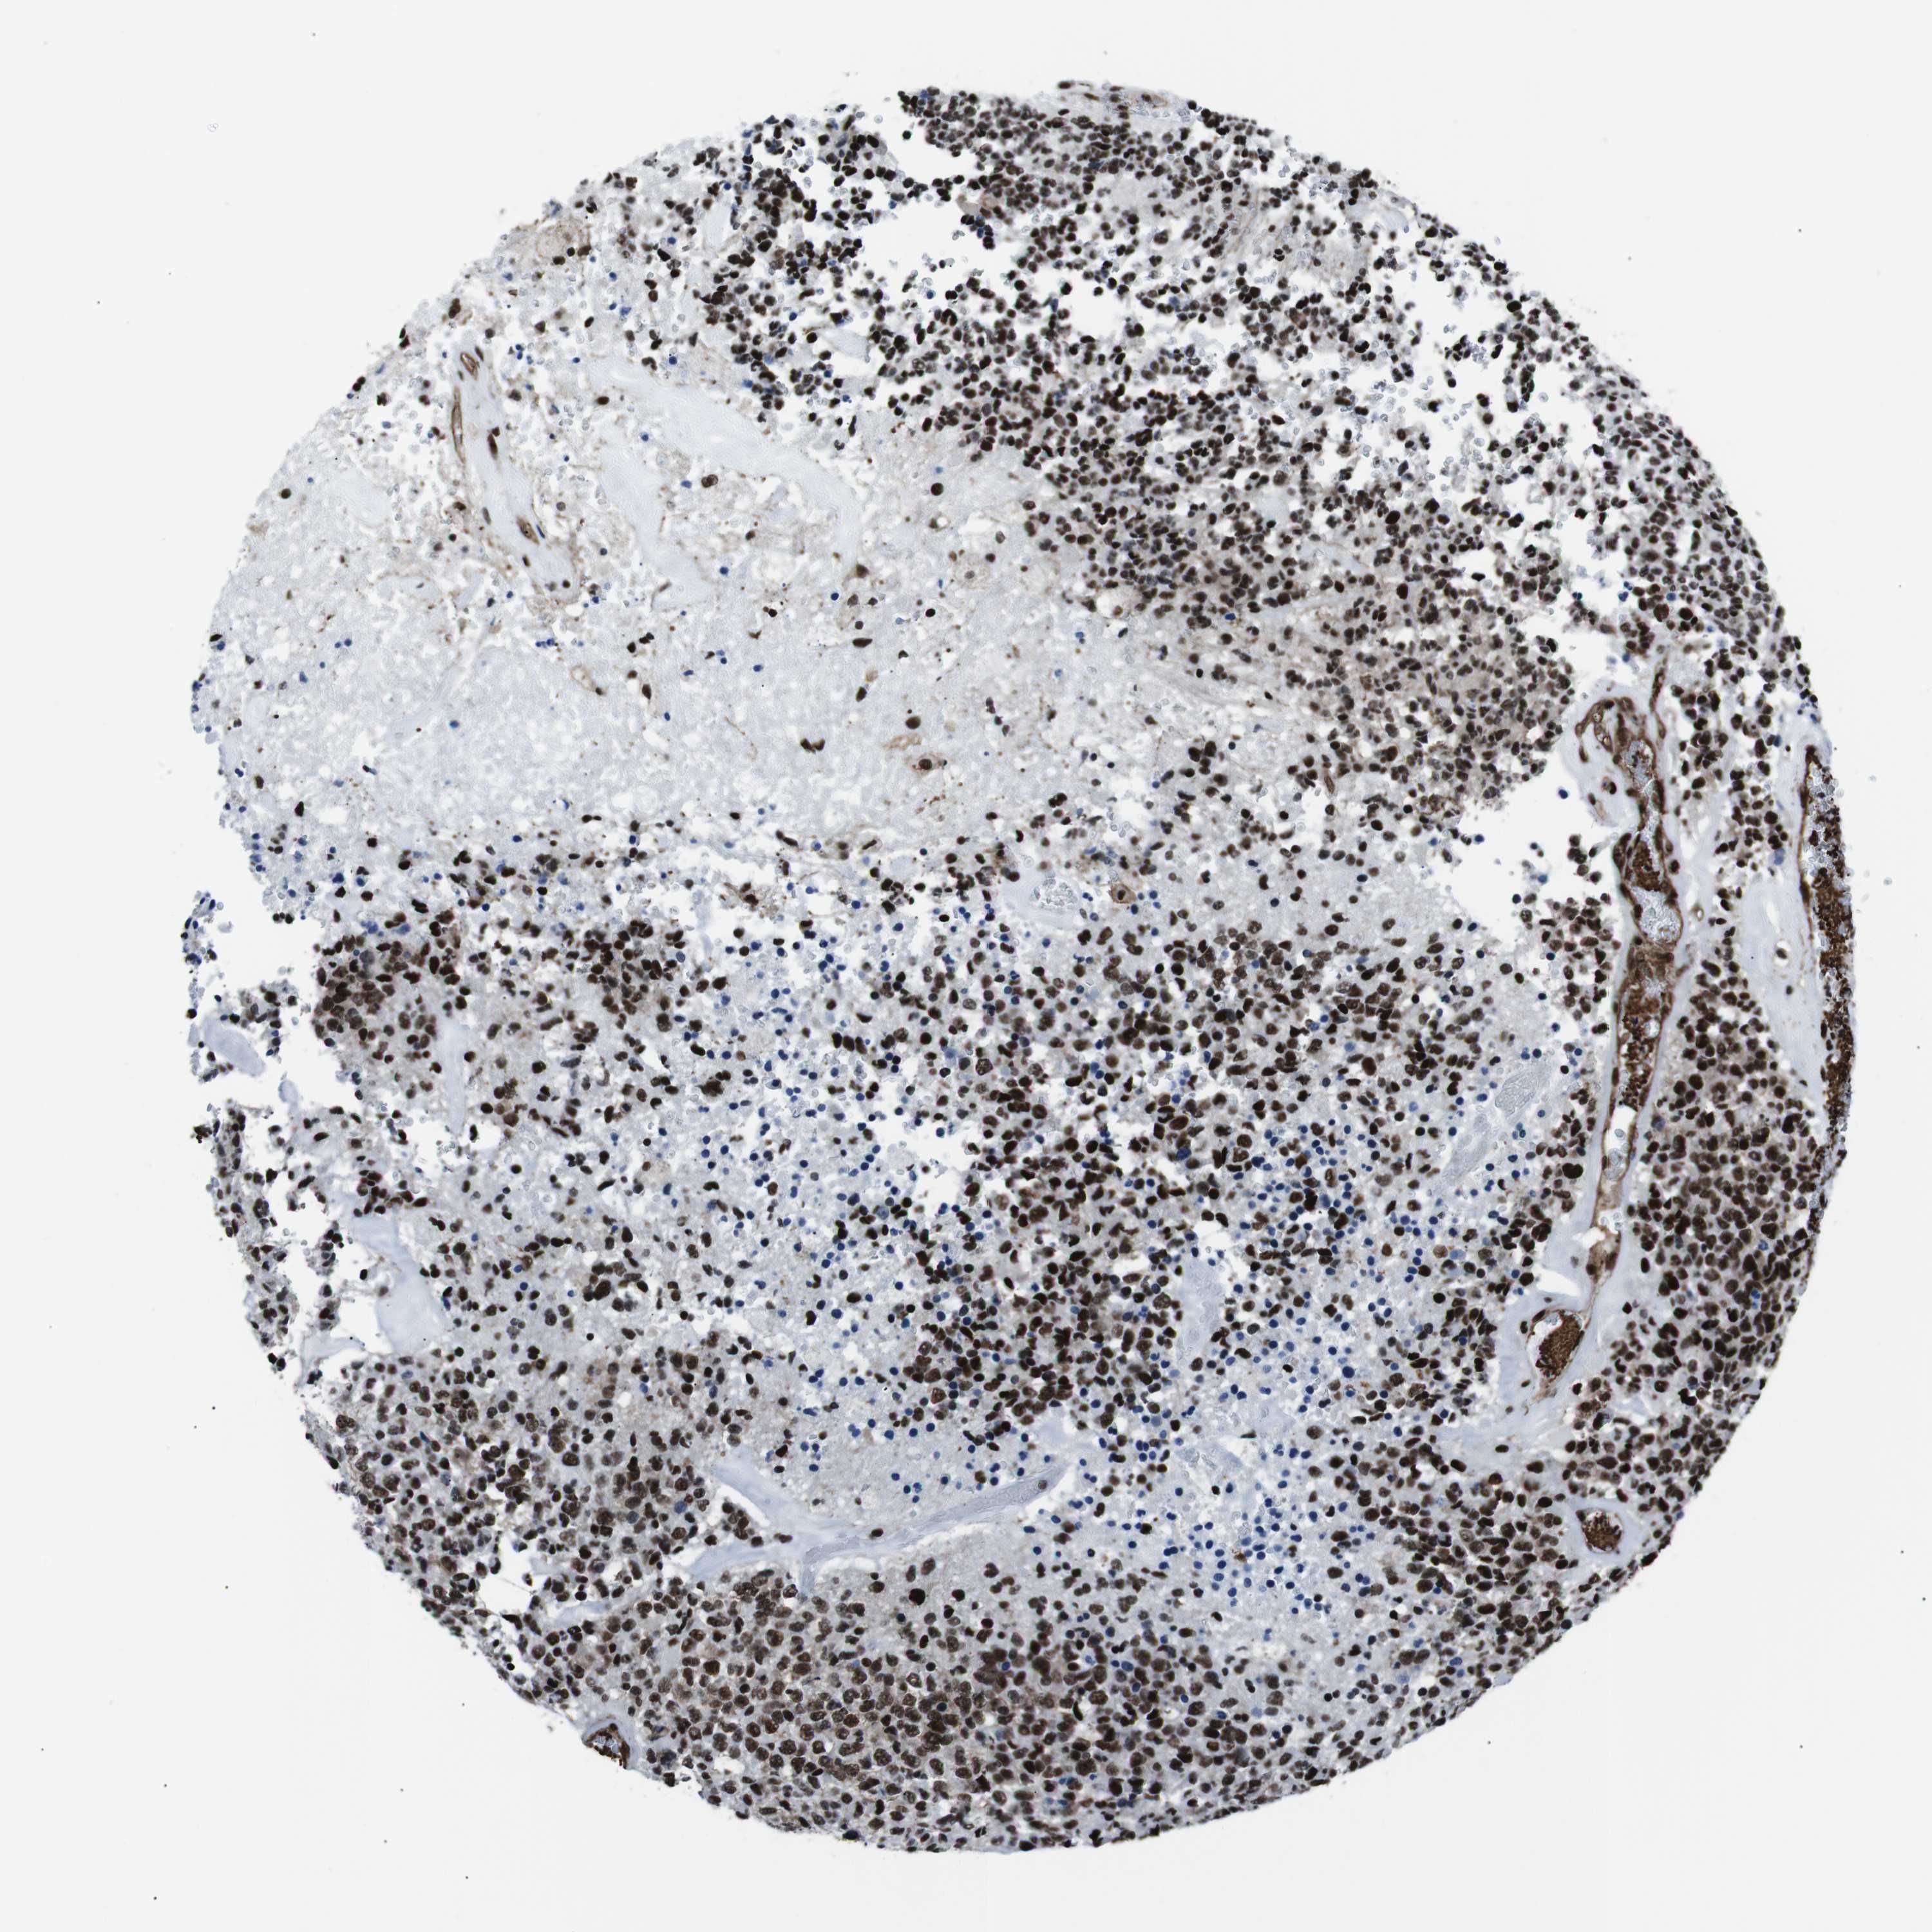

GLIOMA - Protein expressioni

A mouse-over function shows sample information and annotation data. Click on an image to view it in a full screen mode. Samples can be filtered based on level of antibody staining by selecting one or several of the following categories: high, medium, low and not detected. The assay and annotation is described here.

Note that samples used for immunohistochemistry by the Human Protein Atlas do not correspond to samples in the TCGA dataset.

Antibody stainingi

Antibody staining in the annotated cell types in the current human tissue is reported as not detected, low, medium, or high, based on conventional immunohistochemistry profiling in selected tissues. This score is based on the combination of the staining intensity and fraction of stained cells.

Each image is clickable and will lead to virtual microscopy that enables deeper exploration of all samples and also displays staining intensity scores, fraction scores and subcellular localization as well as patient and tissue information for each sample.

Antibody HPA041057

Antibody HPA058707

Antibody CAB011532

Staining

High

Medium

Low

Not detected

Intensity

Strong

Moderate

Weak

Negative

Quantity

>75%

75%-25%

<25%

None

Location

Nuclear

Cytoplasmic/membranous

Cytoplasmic/membranous,nuclear

Glioma, malignant, Low grade

Glioma, malignant, High grade